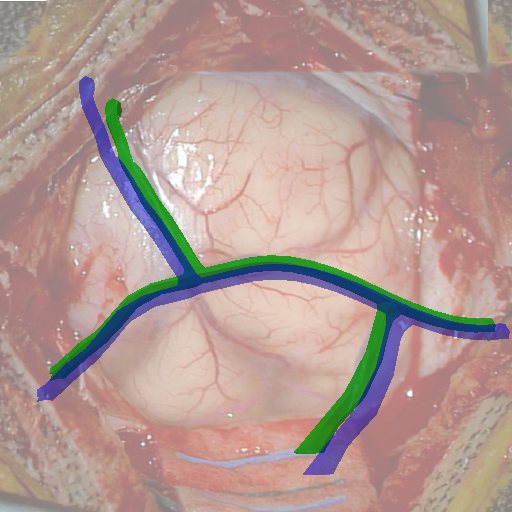

We tested our method retrospectively on 6 clinical datasets from 6 patients (cases) (see Fig. 5). These consisted of preoperative T1 contrast MRI scans and intraoperative images of the brain surface after dura opening. Cortical vessels around the tumors were segmented and triangulated to generate 3D meshes using 3D Slicer. We generated 100 poses for each 3D mesh (i.e.: each case) and used a total of 15 unique textures from human brain surfaces (different from our 6 clinical datasets) for synthesis using . In order to account for potential intraoperative brain deformations [4] we augment the textured projection with elastic deformation [21] resulting in approximately 1500 images per case. The surgical images of the brain (left image of the stereoscopic camera) were acquired with a Carl Zeiss surgical microscope. The ground-truth poses were obtained by manually aligning the 3D meshes on their corresponding images.

Test and Comparison on Clinical Images

We compared our method (Ours) with segmentation-based methods (ProbSEG) and (BinSEG) [7]. These methods use learning-based models to extract binary images and probability maps of cortical vessels to drive the registration. We report in Tab. 1 the distances between the ground truth and estimated poses. Our method outperformed ProbSEG and BinSEG with an average ADD error of mm compared to mm and mm, respectively. Our errors remain below clinically measured neuronavigation errors reported in [4], in which a mm average initial registration error was measured in 15 craniotomy cases using intraoperative ultrasound. Our method outperformed ProbSEG in 5 cases out of 6 and BinSEG in all cases and remained within the clinically measured errors without the need to segment cortical vessels or select landmarks from the intraoperative image. Our method also showed fast intraoperative computation times. It required an average of only milliseconds to predict the pose (tested on research code on a laptop with NVidia GeForce GTX 1070 8GB without any specific optimization), suggesting a potential use for real-time temporal tracking.

Fig. 5 shows our results as Augmented Reality views with bounding boxes and overlaid meshes. Our method produced visually consistent alignments for all 6 clinical cases without the need for initial registration. Because our current method does not account for brain-shift deformation, our method produced some misalignment errors. However, in all cases, our predictions are similar to the ground truth.